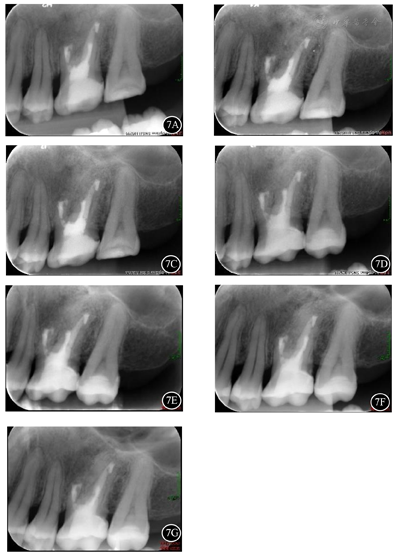

术后定期复查,无诉不适。口内检查:26叩(-),无明显松动,局部牙龈及黏膜未见明显异常(图6)。7B复查根尖片示26根尖区骨密度较术前明显增加(图7)。

面照;B:术后10个月26颊面照;C:术后4年26

面照;D:术后4年26颊面照;E:术后5年26

面照;F:术后5年26颊面照;G:术后5年牙列正面照

术后2年CBCT示:26根尖部分切除,形态平钝,根管倒充填致密;根尖区骨密度较术前明显增加,但其上方至左侧上颌窦底壁以及颊侧骨皮质仍见缺损(图8A、图8B)。术后4年与术后5年CBCT影像表现基本同术后2年(图8C,图8D,图8E,图8F)。

26根尖区骨密度较术前明显增加,但根尖区颊侧骨皮质连续性部分中断,根据Penn影像学分类属于有限愈合。一般认为,无临床症状,并且影像学分类为完全愈合或有限愈合者,可视为成功。故本病例最终评价为成功。其上方至左侧上颌窦底壁存在骨质缺损,考虑为左上颌窦炎行左上颌窦根治术的术后表现。